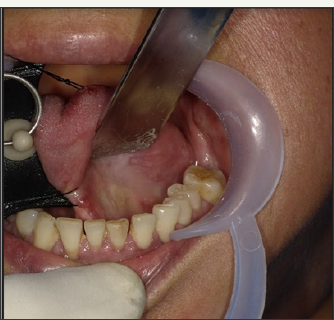

A 58 year old female reported with a chief complaint of intermittent swelling in left submandibular region. The swelling was related to meals and persisted for 2-3 hours after food. It was variable in size and occurrence. On examination, there was mild swelling in submandibular region (Figure 1). Ductal orifice was slightly reddish and tender signifying inflammation. Expressed saliva was normal in appearance and consistency but the salivary flow was relatively reduced compared to contra lateral side. Clinical diagnosis of left submandibular sialolith was made. A computerised tomogram revealed a 2.4mm radiopaque mass in anterior part of the left Wharton's duct (Figure 2a-2c). However, the calculus was not visible or palpable. The sialolith was removed intra orally under local anesthesia. The surgical technique has already been discussed (Figure 3-7).

Figure 3: Tongue and ductal region retracted with sutures.